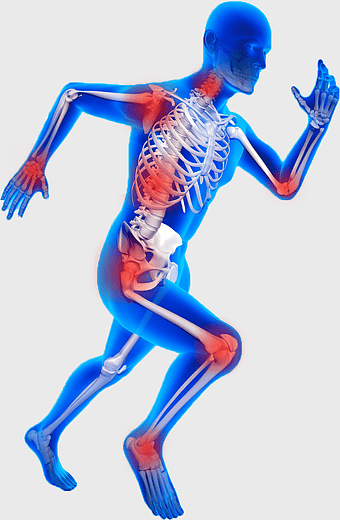

blue man running anatomy, elastic therapeutic tape for pain, True Balance Chiropractic running therapy, human body joint pain, athletic injury recovery, skeletal health visual, mobility rehabilitation physics -